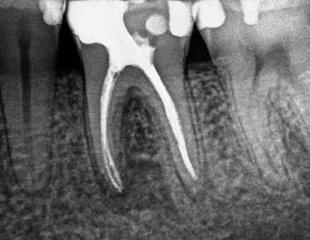

1. a-n. ábrák: Preoperatív CBCT-felvétel a bal alsó 6-os (3.6) fogról. Az axialis (a), coronalis (b) és sagittalis (c) nézeteken a mezialis és distalis gyökerek apicalis harmada körül sugáráteresztő zóna és ép buccalis corticalis csont látható. Egy olyan sablont terveztünk, amely jelezte a csontablak határait az apicalis terület pontos elérése érdekében (d). A mikrosebészeti bevatkozás során a sablont a helyére illesztettük (e), a csontablak határait megjelöltük (f) egy Piezotome CUBE LED kézi-darabba fogott fűrésszel, majd kivágtuk és eltávolítottuk (g és h) az apicalis területhez történő hozzáférés, illetve a mezialis és distalis gyökerek rezekciójának, retrográd preparációjának és retrográd gyökértömésének elvégzése érdekében (i). Végezetül a csontablakot visszaillesztettük és kollagén szivaccsal stabilizáltuk (j). A műtét után közvetlenül készített röntgenfelvétel a 3.6-os fogról (k). A kétéves kontroll során készített CBCT-felvétel: axialis (l), coronalis (m) és sagittalis (n) nézetek.

Egy 63 éves páciens korábban már kezelt bal alsó első nagyőrlőfogából (3.6) eredő mérsékelt fájdalom miatt kereste fel rendelőnket. A kórtörténetében panasza szempontjából releváns információ nem szerepelt. Az elkészült CBCT-felvételen a korábbi kezelések során észre nem vett, jelenleg feltáratlan meziobuccalis csatornát, valamint a mezialis és distalis gyökerek körül kialakult periapicalis elváltozást, és ezt a léziót borító intakt buccalis corticalis csontlemezt láttunk.

Klinikai vizsgálat során vertikális kopogtatási érzékenységet jelzett. A fog körül mérhető szondázási mélység és a fogmobilitás fiziológiás volt. A CBCT-felvételen nem észleltünk a csontos regeneráció megindulására utaló jeleket (1. a–c. ábrák). A korábban gyökérkezelt, gyökértömött és revideált 3.6-os fog esetében az alábbi diagnózis került felállításra: periodontitis periapicalis symptomatica. A panaszokat okozó fog további ellátása során navigált endodonciai mikrosebészetet kívántunk alkalmazni. Az alsó állcsontról intraorális szkent (TRIOS, 3Shape) készítettünk, és a felszíni topográfiát tartalmazó STL fájlt, valamint a CBCT-felvétel készítése során nyert DICOM fájlokat a Blue Sky Bio szoftver segítségével egyesítettük. A sebészi sablon megtervezésére az így kapott háromdimenziós képet használtuk. A sablon kialakítása során arra törekedtünk, hogy a sablon egyértelműen meghatározza a gyökércsúcsi terület eléréséhez szükséges csontablak határait (1. d. ábra)